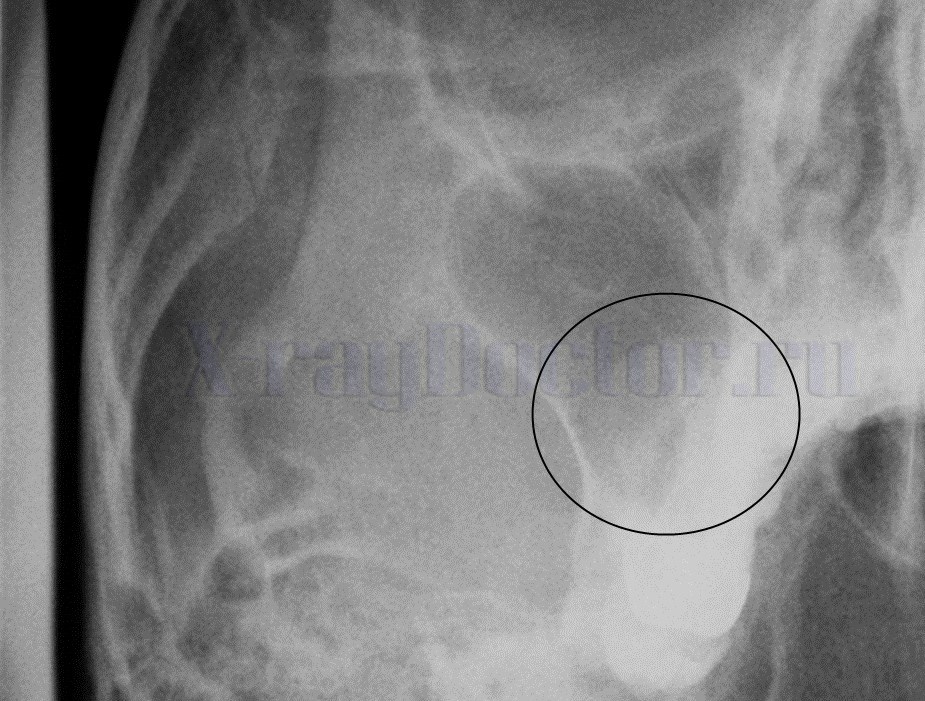

На представленной рентгенограмме придаточных пазух носа визуализируется снижение пневматизации левой верхнечелюстной пазухи в нижней трети с верхним горизонтальным уровнем. Заключение: рентген-признаки левостороннего верхнечелюстного синусита (гайморита).

На снимке выше можно проследить пристеночное затемнение обеих гайморовых пазух. Описание его приведет к логическому заключению о двустороннем гайморите.